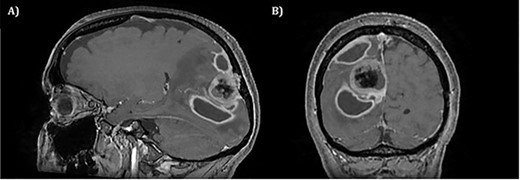

The operation was successful with a post-operative MRI within 48 h demonstrating complete resection of the tumour and resolution of the cystic lesions, but persisting intraparenchymal oedema (Fig. 3). The patient had an uncomplicated two-day stay in a neurosurgery high dependency unit postoperatively before being stepped down to the general neurosurgery ward. She was reviewed by the microbiology team and worked up for the source of infection. Blood cultures, urine cultures, CXR and transthoracic echocardiography were all negative for a source of infection. Intra-operative pus cultures isolated MSSA. The histopathology of the tumour was Meningioma WHO Grade 1 with large areas of necrosis and secondary abscess formation. She was discharged feeling well 5 days later after a satisfactory biochemical and clinical response. She was given a weaning course of steroids and a 6-week course of intravenous ceftriaxone via a PICC line as an outpatient as per microbiology advice. Ophthalmology assessment 3 months after discharge confirmed a left inferior quadrantonopia and preserved visual acuity. Repeat MRI and clinic review 8 weeks later showed no radiological residual tumour or oedema (Fig. 4), and the patient’s limb function recovered completely but had ongoing visual symptoms.

T1 weighted axial MRI postgadolinium enhancement within 48 h post-operatively. Small amount of enhancement within the surgical bed remains. Good resection margins with vasogenic oedema. This may represent a small residual. The rim-enhancing cystic lesions appear to have resolved.

T1 weighted axial MRI post-gadolinium enhancement 8 weeks postdischarge. Right occipital postsurgical appearances are again demonstrated with reduction in the extent of vasogenic oedema. The enhancing rim that was present previously has retracted, with only focal curvilinear enhancement now evident in the right occipital lobe. These appearances are likely postsurgical/treatment related, and there is no convincing residual or recurrent disease.